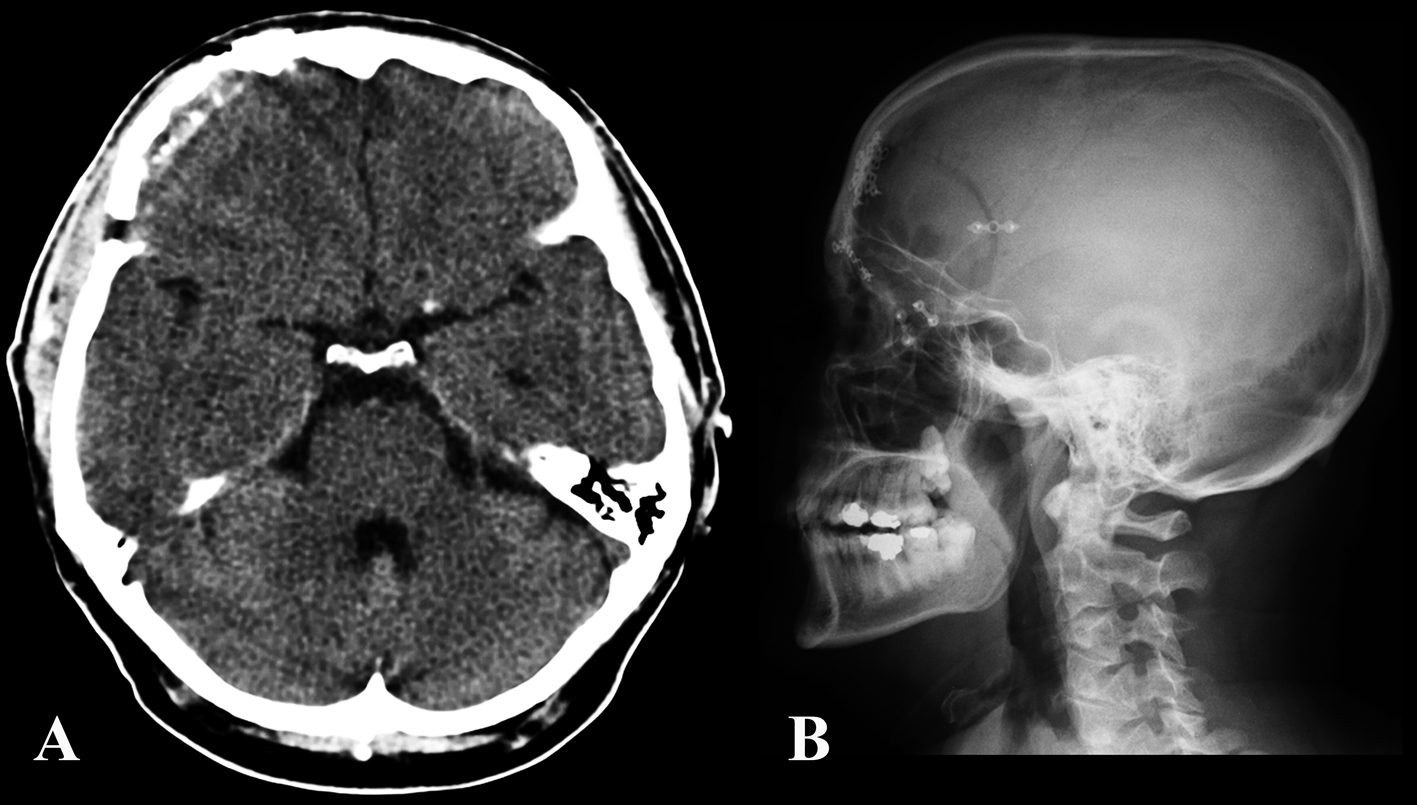

The patient’s postoperative course was uneventful. At 6 months follow up, the patient reported no more episodes of headache (Fig. 4, 5).

![]() Click for large image | Figure 4. Post-operative CT (A) and skull x-plain film (B) showing the craniotomy and bony reconstruction. |